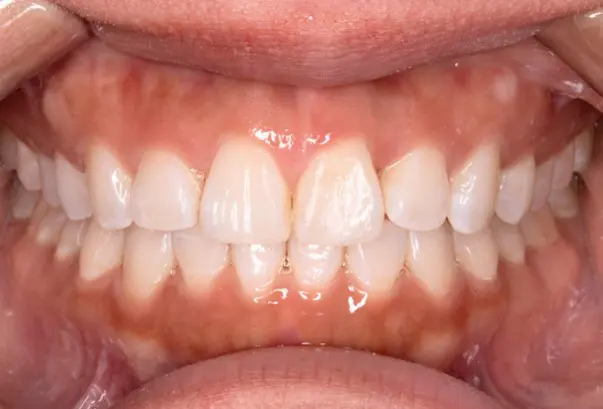

Crossbite

Before

After